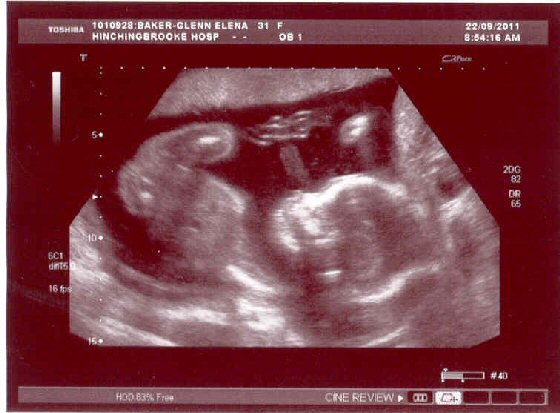

These are the photos taken on 22/09/11: